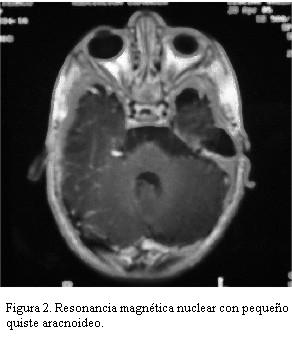

Resonancia magnética nuclear de cráneo que evidencia leve dilatación de los espacios subaracnoideos a predominio bifrontal e interhemisférico así como también del sistema ventricular, con pequeño quiste aracnoideo (figuras 2 y 3). No aumento en la señal en T2 a nivel del globo pálido, núcleo dentado cerebelar y sustancia blanca.